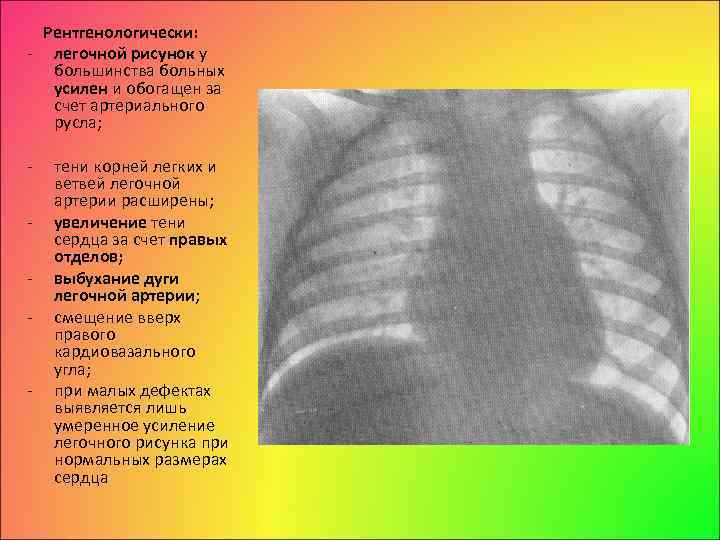

Ячеистая деформация легочного рисунка: медицинская визуализация